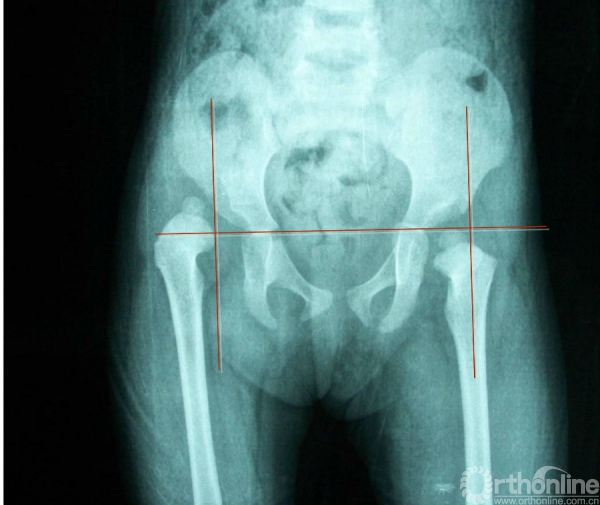

X线检查 外侧线(Calve线)

外侧线(Calve线)即髂翼的外侧面与股骨颈外侧面的弧形连线,正常为连续的。

右髋关节脱位Ⅲ度